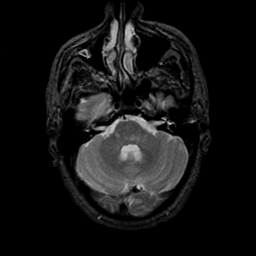

MR Study #9, April 14, 1991 -- Slice #12